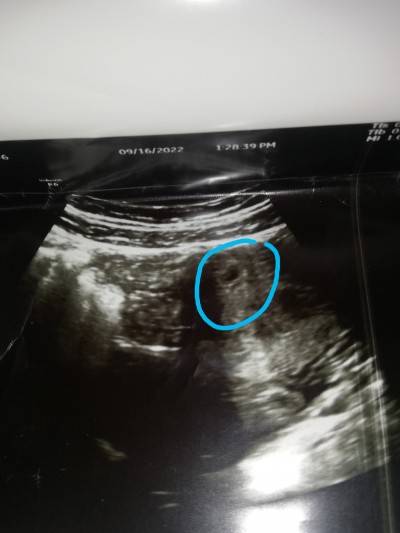

6 haftalık hamileyim bugün gittik kesenin içinde henüz bebek görünmüyor yaşadınız mı ?

Bende gittiğimde ilk kese görünüyodu eşimle emin olamamıştık bebek varmı yokmu diye genede o derece belli değildi bi sonraki gittiğimizde emin olduk sen içini ferah tut kontrolü bekle

8 haftaliktim kese var ama bebek yoktu  bir sonraki hafta gel keseyi alalim dediler keseyi almaya Gittim kalp atisini duyduk cok sukur yavrumuzun suan 9 ayima girdim 20 gune dogum var allahin izniyle korkma kalbini ferah tut dua et bol bol endise etme

Evet bu çok normal benim doktorumda bana aynı şeyi söyledi kese var ama.bebek henüz yok dedi hafta gel dedi. Canım hiç canını sıkma bir sonraki kontrolünde görülecektir.

ayni seyi bende yaşadim ama onlar zaten kesenin durumundan bile anliyorlar. kotu bir sey demediyse icinizi rahat tutun üstelik benim bebislerim ikiz ona ragmen ayni haftalarda gorunmemislerdi

Bende şimdi geldim doktordan 6+1 kese var bebek yok

Bende şuan 6+2 yim 5+6 da gittim ilk muaynemdi kese gözüktü ekranı daha çok büyütüp bebegide gördü ama daha çok küçük yeni beslenmeye başlamış haftaya kalp atışı için gel dedi